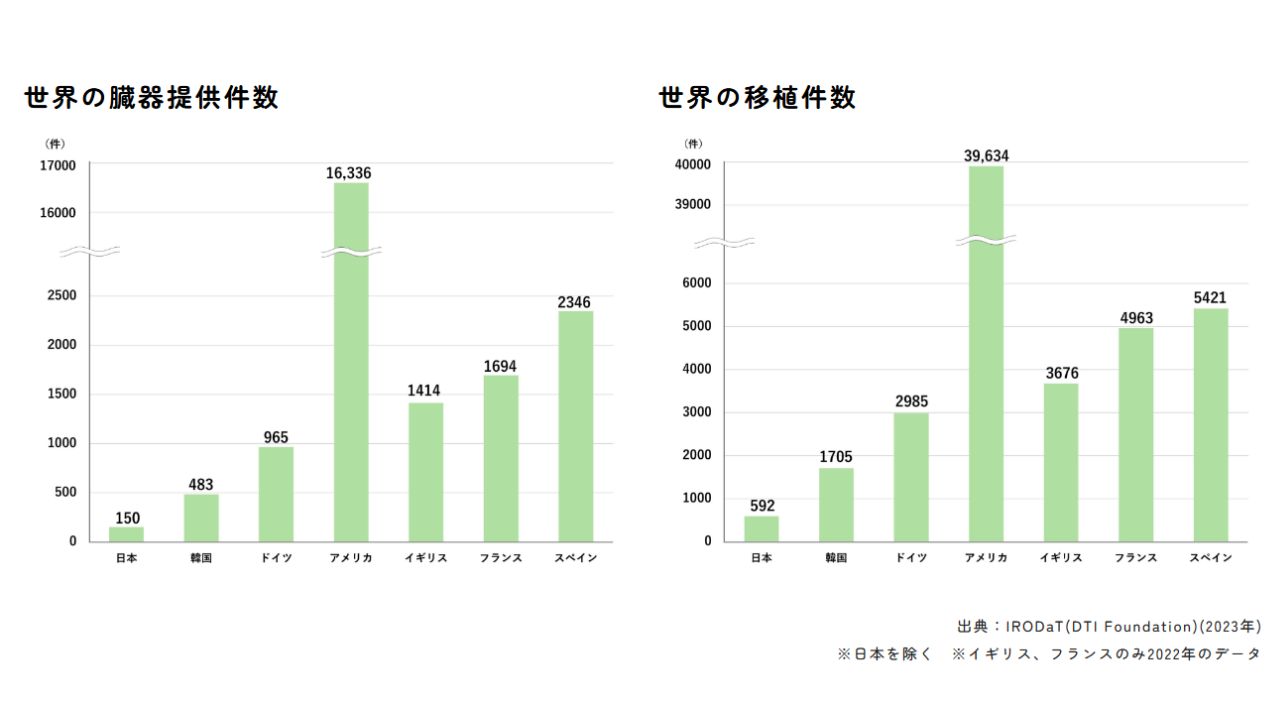

日本臓器移植ネットワークによると、5月時点で心臓移植を待っている人は、800人いる。ただ、提供される心臓の数は、1年で100件ほど。

脳死判定を受けた人からの臓器移植を認める臓器移植法が施行された1997年からあわせて974人が心臓移植を受けたが627人が待機中に亡くなった。

臓器移植の件数は人口が半分以下の韓国が日本のおよそ3倍、アメリカは67倍ほど。

日本は脳死判定を受け、同意が得られた人の臓器を、移植を待つ患者に提供する体制が十分に整っていない。

さらに、移植手術が進む韓国やアメリカと比べ、医師が十分な報酬も得られないことなどから、外科医不足が深刻化している。

これらを解決する制度改革も進まない。